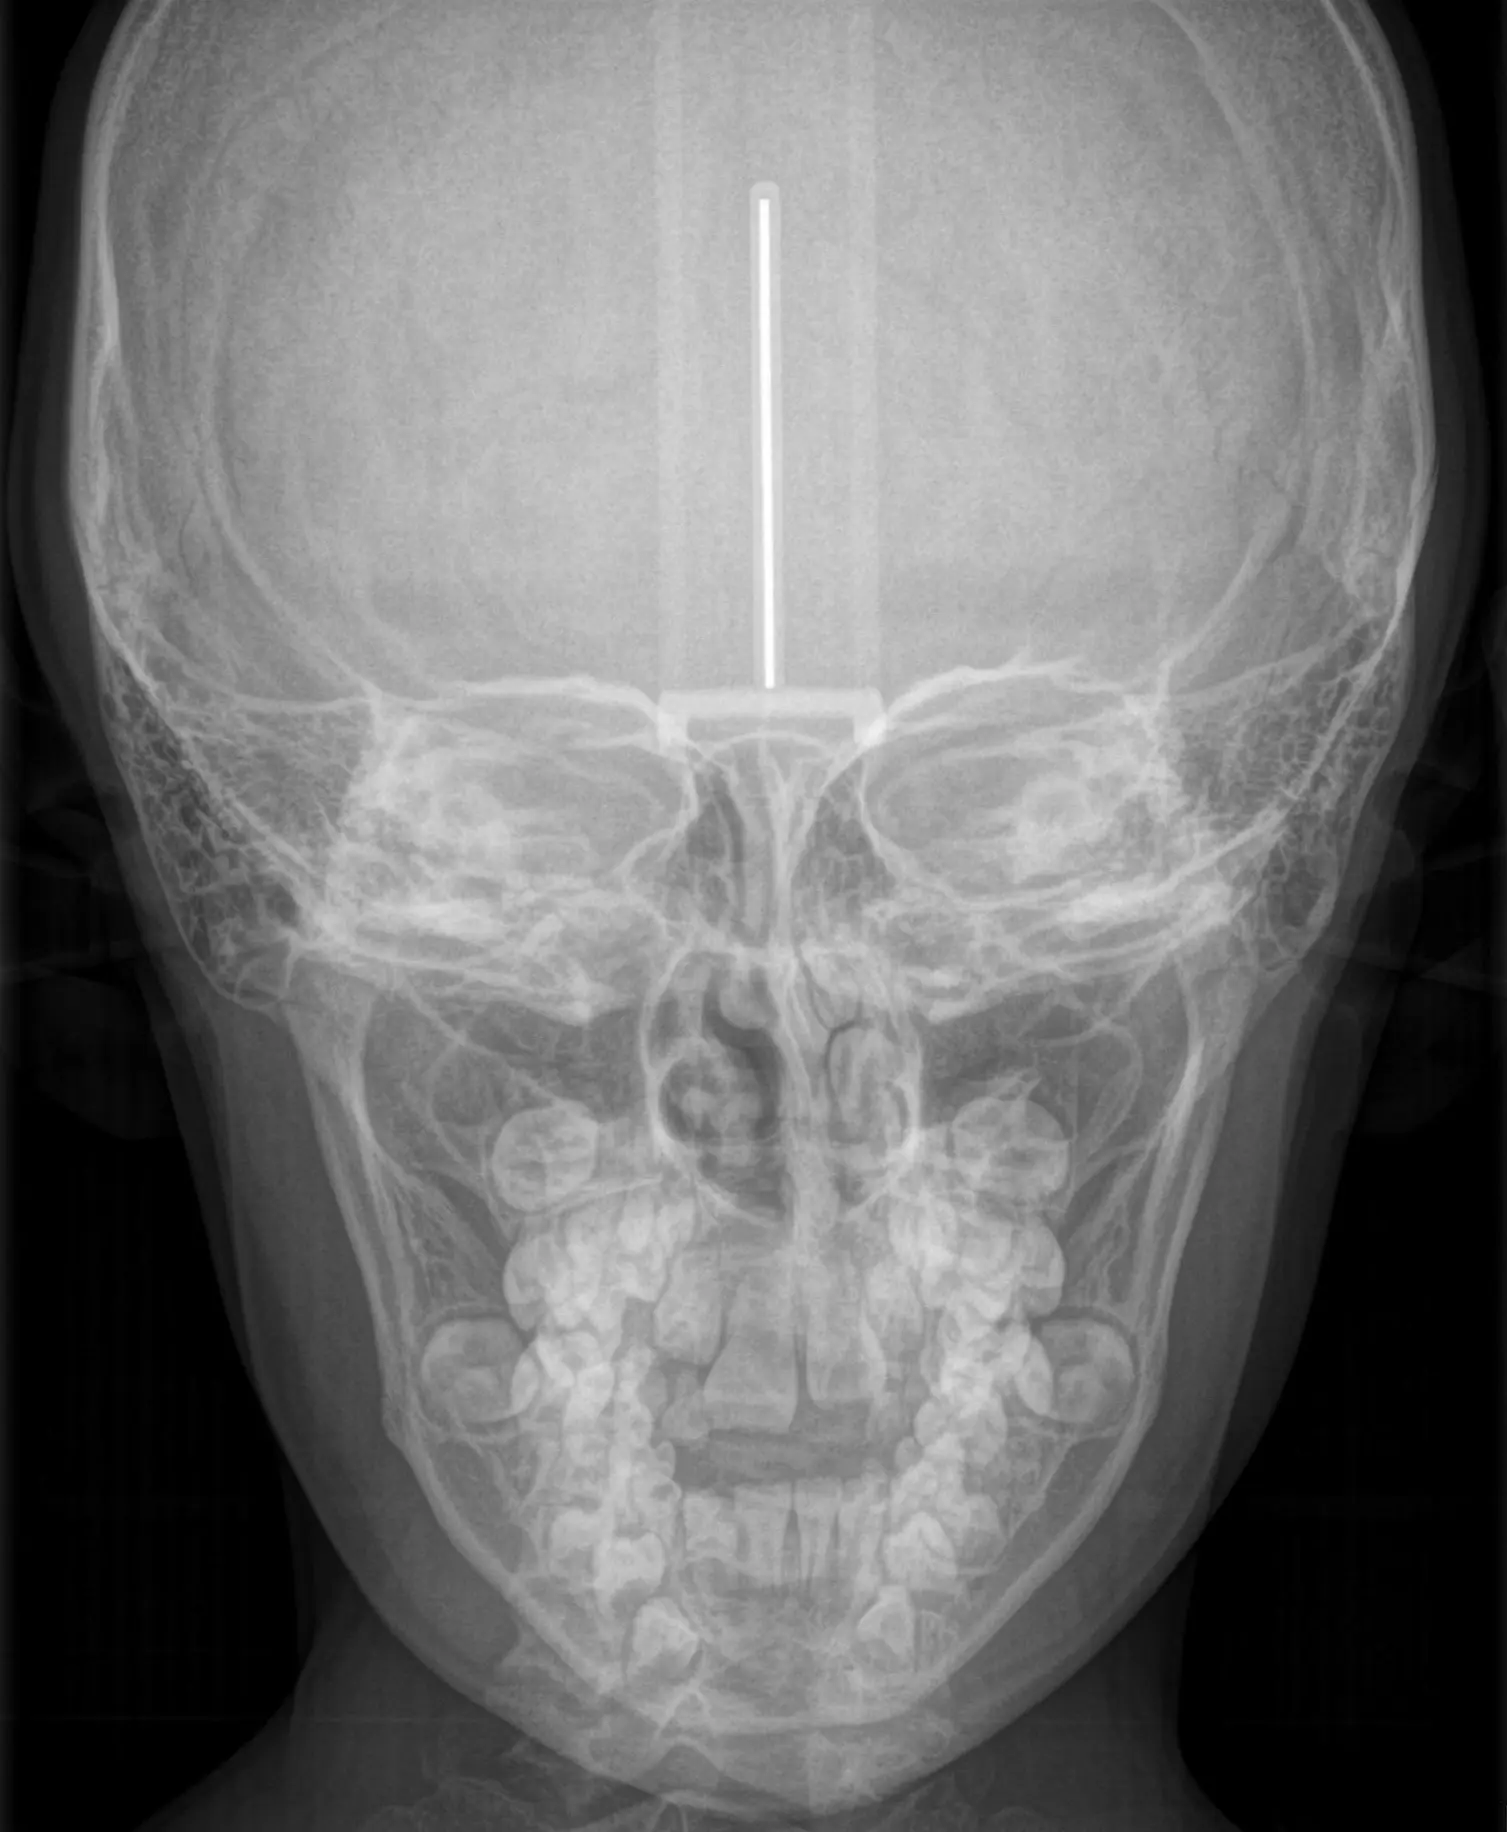

RX ANTEROPOSTERIOR

Nos permite visualizar las estructuras anatómicas en su eje frontal, evaluando su alineación, forma, tamaño y relaciones óseas. Utilizandose para, identificar fracturas, deformaciones o lesiones óseas, evaluar articulaciones y estructuras anatómicas